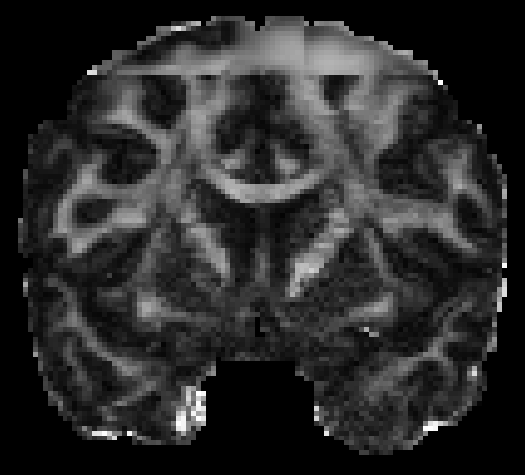

The visualization of inpainted results (showing the whole diffusion tensor for each voxel) generated from different models are demonstrated in Figure 3, where the tensor is represented in RGB coding that colours red, green and blue represent diffusion in the x, y, and z axes respectively. One typical example of reconstruction in the disrupted ROIs has been zoomed for visualization. Compared to the ground truth, TW-BAG is able to generate more distinct orientations following the original distribution and intensity across sagittal, coronal and axial views, which could demonstrate water diffusivity (denoted by eigenvalues of tensor model) more accurately. As indicated in Figure 4, the boundaries and textures of the FA map for TW-BAG are less blurry than the other competing models, validating the effectiveness of TW-BAG from a neuroscience perspective.

To better understand each new component from our proposal, an ablation study was conducted for the gate convolution, brain-aware mechanism and tensor-wise coefficient specific decoder separately. Summaries of the metrics presented in the previous section for each ablation are shown in Table I and Table II, respectively. The baseline model (w/o BAG-TW) was designed as a 3D-UNet and all the experiments included were built on top of that baseline structure. The gate convolution (w/o BA-TW) reached a slightly worse result when compared to the baseline, while the brain-aware mechanism (w/o TW) increased the performance, especially on the scalar metrics. The results suggest that the gate convolution failed to focus on extracting the features from only the valid brain and the brain-aware mechanism tackled this dilemma by introducing a guidance on the foreground. Although the introduction of specifically designed tensor-wise coefficient decoders only increased the MAE and PSNR by a small margin, it decreased the MAE for FA from 0.07 to 0.03 (55% improvement) and the whole-brain FA from 0.0041 to 0.0018 (56% improvement). The scalar metrics prove the effectiveness of the tensor-wise decoders in learning features tailored for each particular coefficient in the tensor model.

III-F Efficiency Study

| (a) Disrupted | (b) GT | (c) 32 | (d) 37 | (e) 42 | (f) 47 |